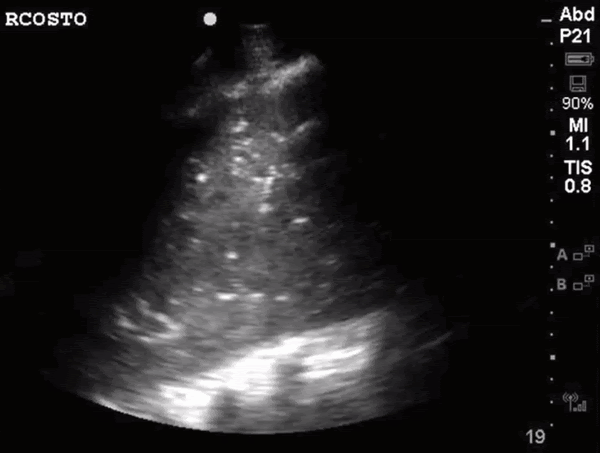

What do we see in this pt’s US?!

Right lung base

• air bronchogram occurs when endobronchial air is visible against a background of increased lung opacity.

• Immobile hyperechoic structure in consolidated or “hepatized” lung → indicating obstructed and trapped air → usually sign of atelectasis

• Mobile hyperechoic structure in consolidated or “hepatized” lung → indicating patent airway ⇒ pathognomonic for pneumonia

Patient’s CT chest came back positive for right sided aspiration pneumonia and right lung collapse secondary to pleural effusions.